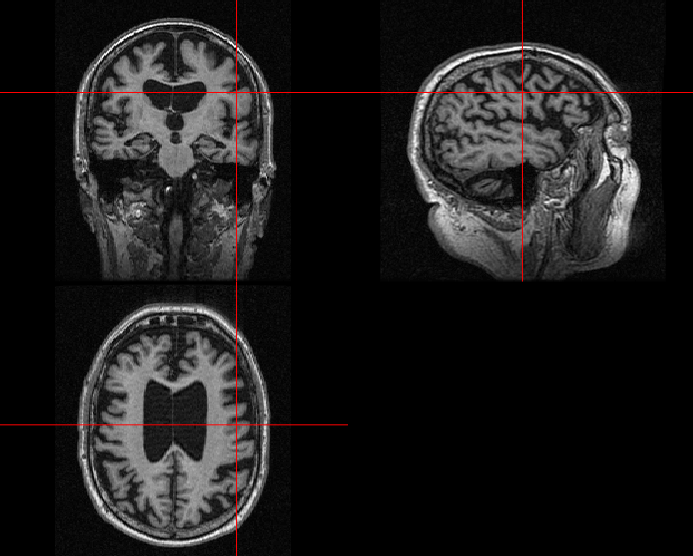

German physicist Alois Alzheimer laid the foundations of most of the modern understanding of the underlying causes of this disorder when he noticed the common biomarkers through histological techniques on the brains of his diseased patients [5]. Recent technologies exist, such as MRI, which helps in visualising atrophy or change in tissue volume of such biomarkers over a period of time, or fMRI, which can identify high-resolution activation of different brain regions during various cognitive tasks [6]. Fig. 1 shows the example of an AD patient’s raw unprocessed brain slice in different planes obtained from MR imaging in a magnetization-prepared rapid gradient-echo (MP-RAGE) sequence.

Refer to caption

(a)

(b)

(c)

Figure 1: MP-RAGE T1 Weighted MR slices: (a) Axial plane (b) Sagittal plane (c) Coronal plane